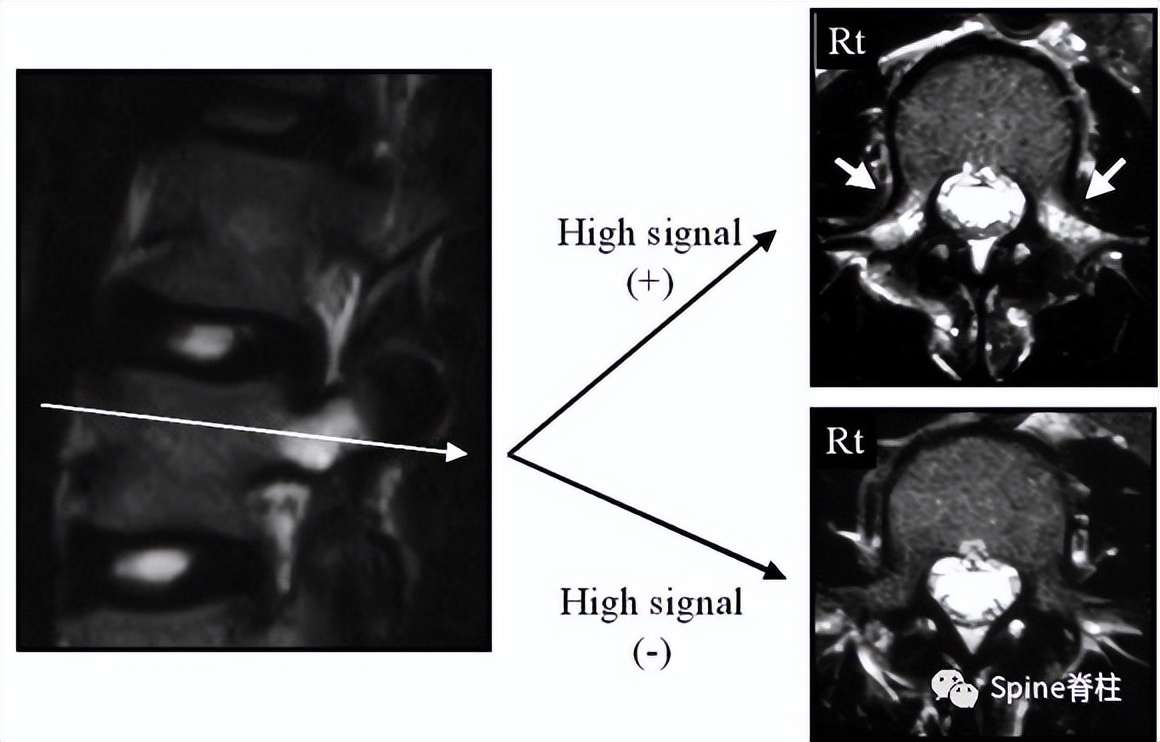

有研究发现磁共振上 椎弓根出现T2高信号改变是青少年和儿童峡部裂的早期诊断征象 。同时, 存在椎弓根高信号改变也是保守治疗后能达到骨性愈合的良好预测指标 (也就是说存在T2椎弓根右高信号改变的峡部裂患者,其峡部裂经保守治疗愈合的可能性大) 。

右上图为椎弓根高信号改变(+),右下图为(-)

左侧为椎弓根水肿阳性,右侧为椎弓根水肿阴性,有研究发现峡部裂伴随着椎弓根水肿,支具固定愈合率更高

Sairyo教授研究发现磁共振上 椎弓根出现T2高信号改变是青少年和儿童峡部裂的早期诊断征象 。同时,存在椎弓根高信号改变也是保守治疗后能达到骨性愈合的良好预测指标(也就是说存在T2椎弓根右高信号改变的峡部裂患者,其峡部裂经保守治疗愈合的可能性大)。

图:右上图为椎弓根高信号改变(+),右下图为(-)